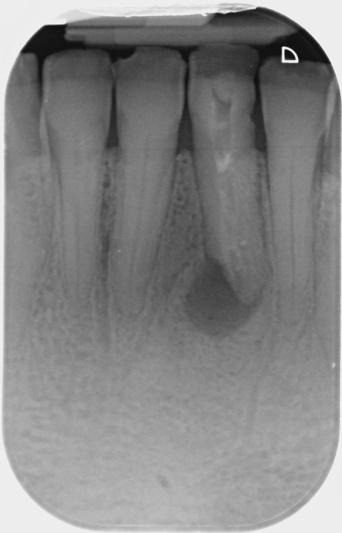

This was an internal referral from my delightful colleague Alison. The patient reported she had root treatment on her LL1 around 10 years ago. It presented with a buccal sinus tract adjacent to the LL1 and was diagnosed as previously initiated root treatment with a chronic apical abscess with possible internal resorption. A CBCT scan was taken to help assess the restorability of this tooth.

- There is a large, irregularly shaped root canal with fragments of dressing within it.

- It is unclear whether this canal has been partially shaped or if there is a degree of resorption resulting in its widened appearance, if this is resorption the entire length of the root canal is affected.

- There is mild apical resorption of the LL1 resulting in two apical exit points.

- There is a well-defined area of apical radiolucency measuring approximately 5mm (w) x 3mm (d) x 9mm (h).

- There is dehiscence of the labial cortex overlying the root of the LL1 (BIG LESION!)

Immediate post-op IOPA

Overall a nice result with this one perhaps a little more sealer extruded than I would ideally like to see, but it shouldn’t pose an issue due to its biocompatibility. A 1-year CBCT review is planned, so I’ll include this once I have it.